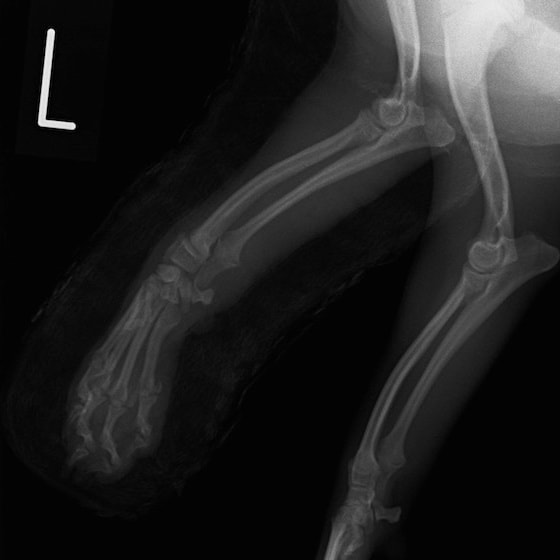

症例3:キルシュナーワイヤーのピンニングによる整復

ペルシャ猫 11ヶ月齢 雄

他院にて左大腿骨遠位の成長板骨折(salter-harrisⅠ型)が認められており、治療相談を目的として来院。当院にて、キルシュナーワイヤーを用いたピンニングにより骨折部位の整復を行いました。術後の経過は良好で、現在も経過観察中です。

術前レントゲン

術後レントゲン